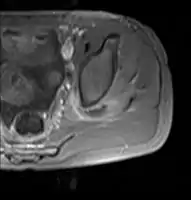

| Transverse T2 magnetic resonance imaging section through the hip region showing abscess collection in a patient with pyomyositis. | |

CT exam showing a multiloculated fluid collection in the left gluteus minimus muscle found to be a staph aureus pyomyositis in a 12-year-old healthy boy. Axial T1 weighted fat suppressed post IV gadolinium contrast enhanced MRI image showing a mutliloculated bacterial abscess in the left gluteal muscle which grew Staphylococcus aureus (methicillin sensitive) thought to be due to tropical pyomyositis.

Axial T1 weighted fat suppressed post IV gadolinium contrast enhanced MRI image showing a mutliloculated bacterial abscess in the left gluteal muscle which grew Staphylococcus aureus (methicillin sensitive) thought to be due to tropical pyomyositis. Coronal fat suppressed post contrast image showing a multiloculated bacterial abscess in the left gluteus minimus muscle due to tropical pyomyositis.